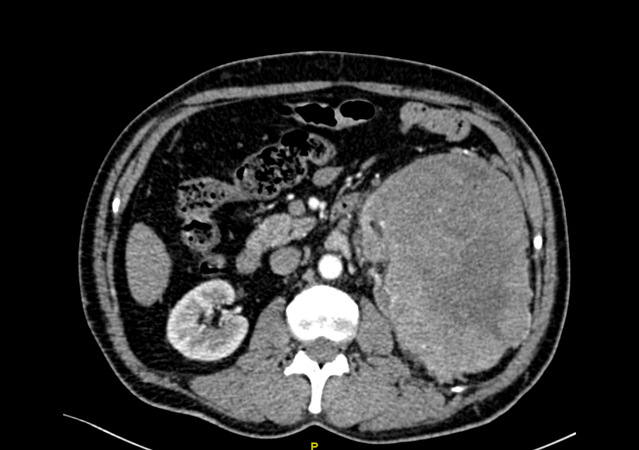

经过CT等检查,发现陈先生的左边肾脏上长了一个巨大的肿瘤,大小约16.6cm*11.1cm,也正是因为这个原因,导致了腰痛、血尿、排尿困难等一系列症状。

金沙娱乐城app 泌尿外科团队仔细分析了患者的病情、症状以及影像学检查,发现陈先生体内的这一颗“定时炸弹”比既往所处理过的任何一例肾脏肿瘤都要庞大,而且已经充满了患者的后腹腔,更为棘手的问题在于肿瘤恶性可能极大,供养这颗肿瘤生长的血管,也密密麻麻的盘曲在肿瘤周围,给手术治疗带来了极大的困难。如果按照既往的治疗方案,对于如此巨大的肾脏肿瘤,而且同时合并肿瘤出血带来的粘连等一系列困难,往往选择开放手术,也就是老百姓口中的“开大刀”。但是众所周知,开放手术存在切口长、手术创伤大、术后恢复缓慢以及术后并发症多等诸多缺点。思虑再三,经过泌尿外科科内讨论后,最终决定给陈先生实行了腹腔镜下微创手术,减少手术带来的损害及痛苦。